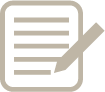

- 妊娠10ヶ月 38週0日 撮影日:2017年03月02日

- 妊娠10ヶ月 38週0日 撮影日:2017年03月02日

- 妊娠10ヶ月 38週0日 撮影日:2017年03月02日